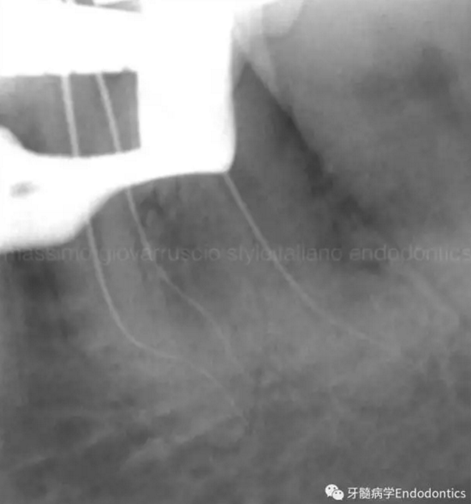

圖9.當(dāng)遇到了根尖方向的阻力,退出銼,使用銼預(yù)彎鉗(Endobender)平滑的預(yù)彎銼尖部的2mm,將銼上的硅膠止動(dòng)片的方向指示調(diào)成朝向銼彎曲的方向,這樣你就可以繞過障礙形成通路了。

圖10.探查時(shí)小心地使用給手表上發(fā)條的動(dòng)作使銼向前通過障礙。遇到阻礙時(shí),稍微回拉銼,將銼尖轉(zhuǎn)向新的方向,向根尖方向扭動(dòng),觀察銼是否前進(jìn)。如果沒有,將銼回拉,重新將彎曲的銼尖改變方向,觀察是否通過。不斷重復(fù),觀察是否前進(jìn),直至通路形成。必須使用根測(cè)儀和X線片檢查在障礙通過后是否到達(dá)了根尖止點(diǎn)。